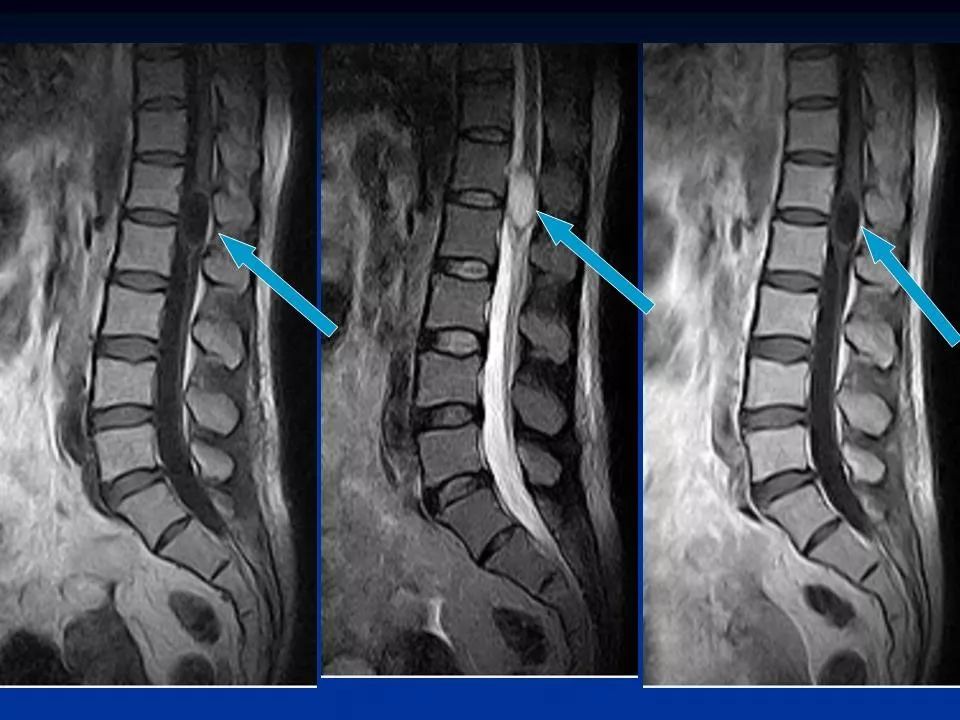

17 种脊髓病变影像解读,你 get 了吗

图片尺寸1080x451